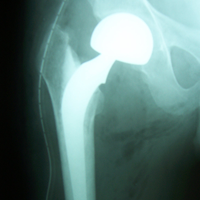

Case:3 Septic Arthritis-THR

2Months Pre-Op

Imm Post-Op

Total Hip Replacement